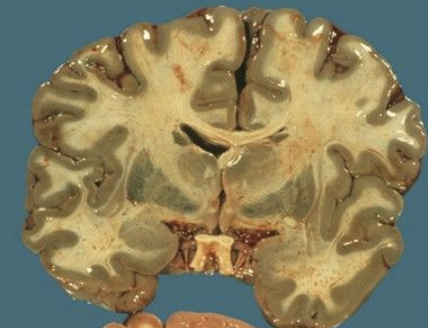

soot in airways, ischemia or hemorrhagic necrosis in globus pallidus and perivascular foci of demyelination in deep white matter

autopsy findings from CM poisoning?

hydrogen sulfide

green discoloration of brain